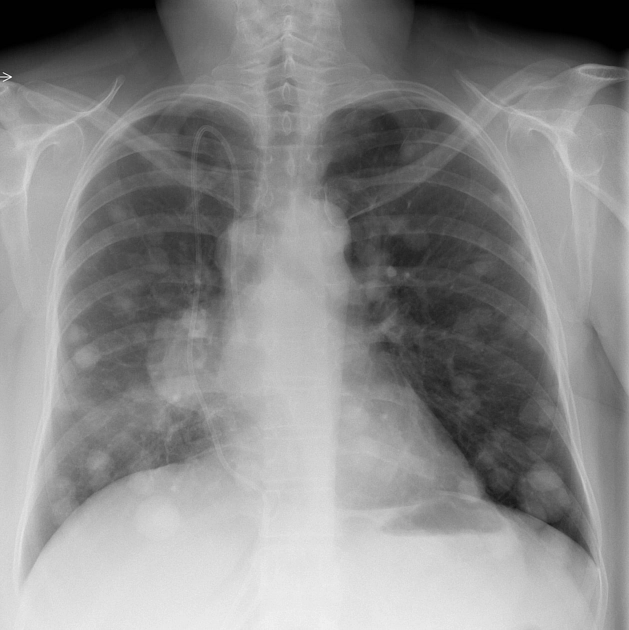

Di căn theo đường máu (Hematogenous Metastases)

16/03/2026